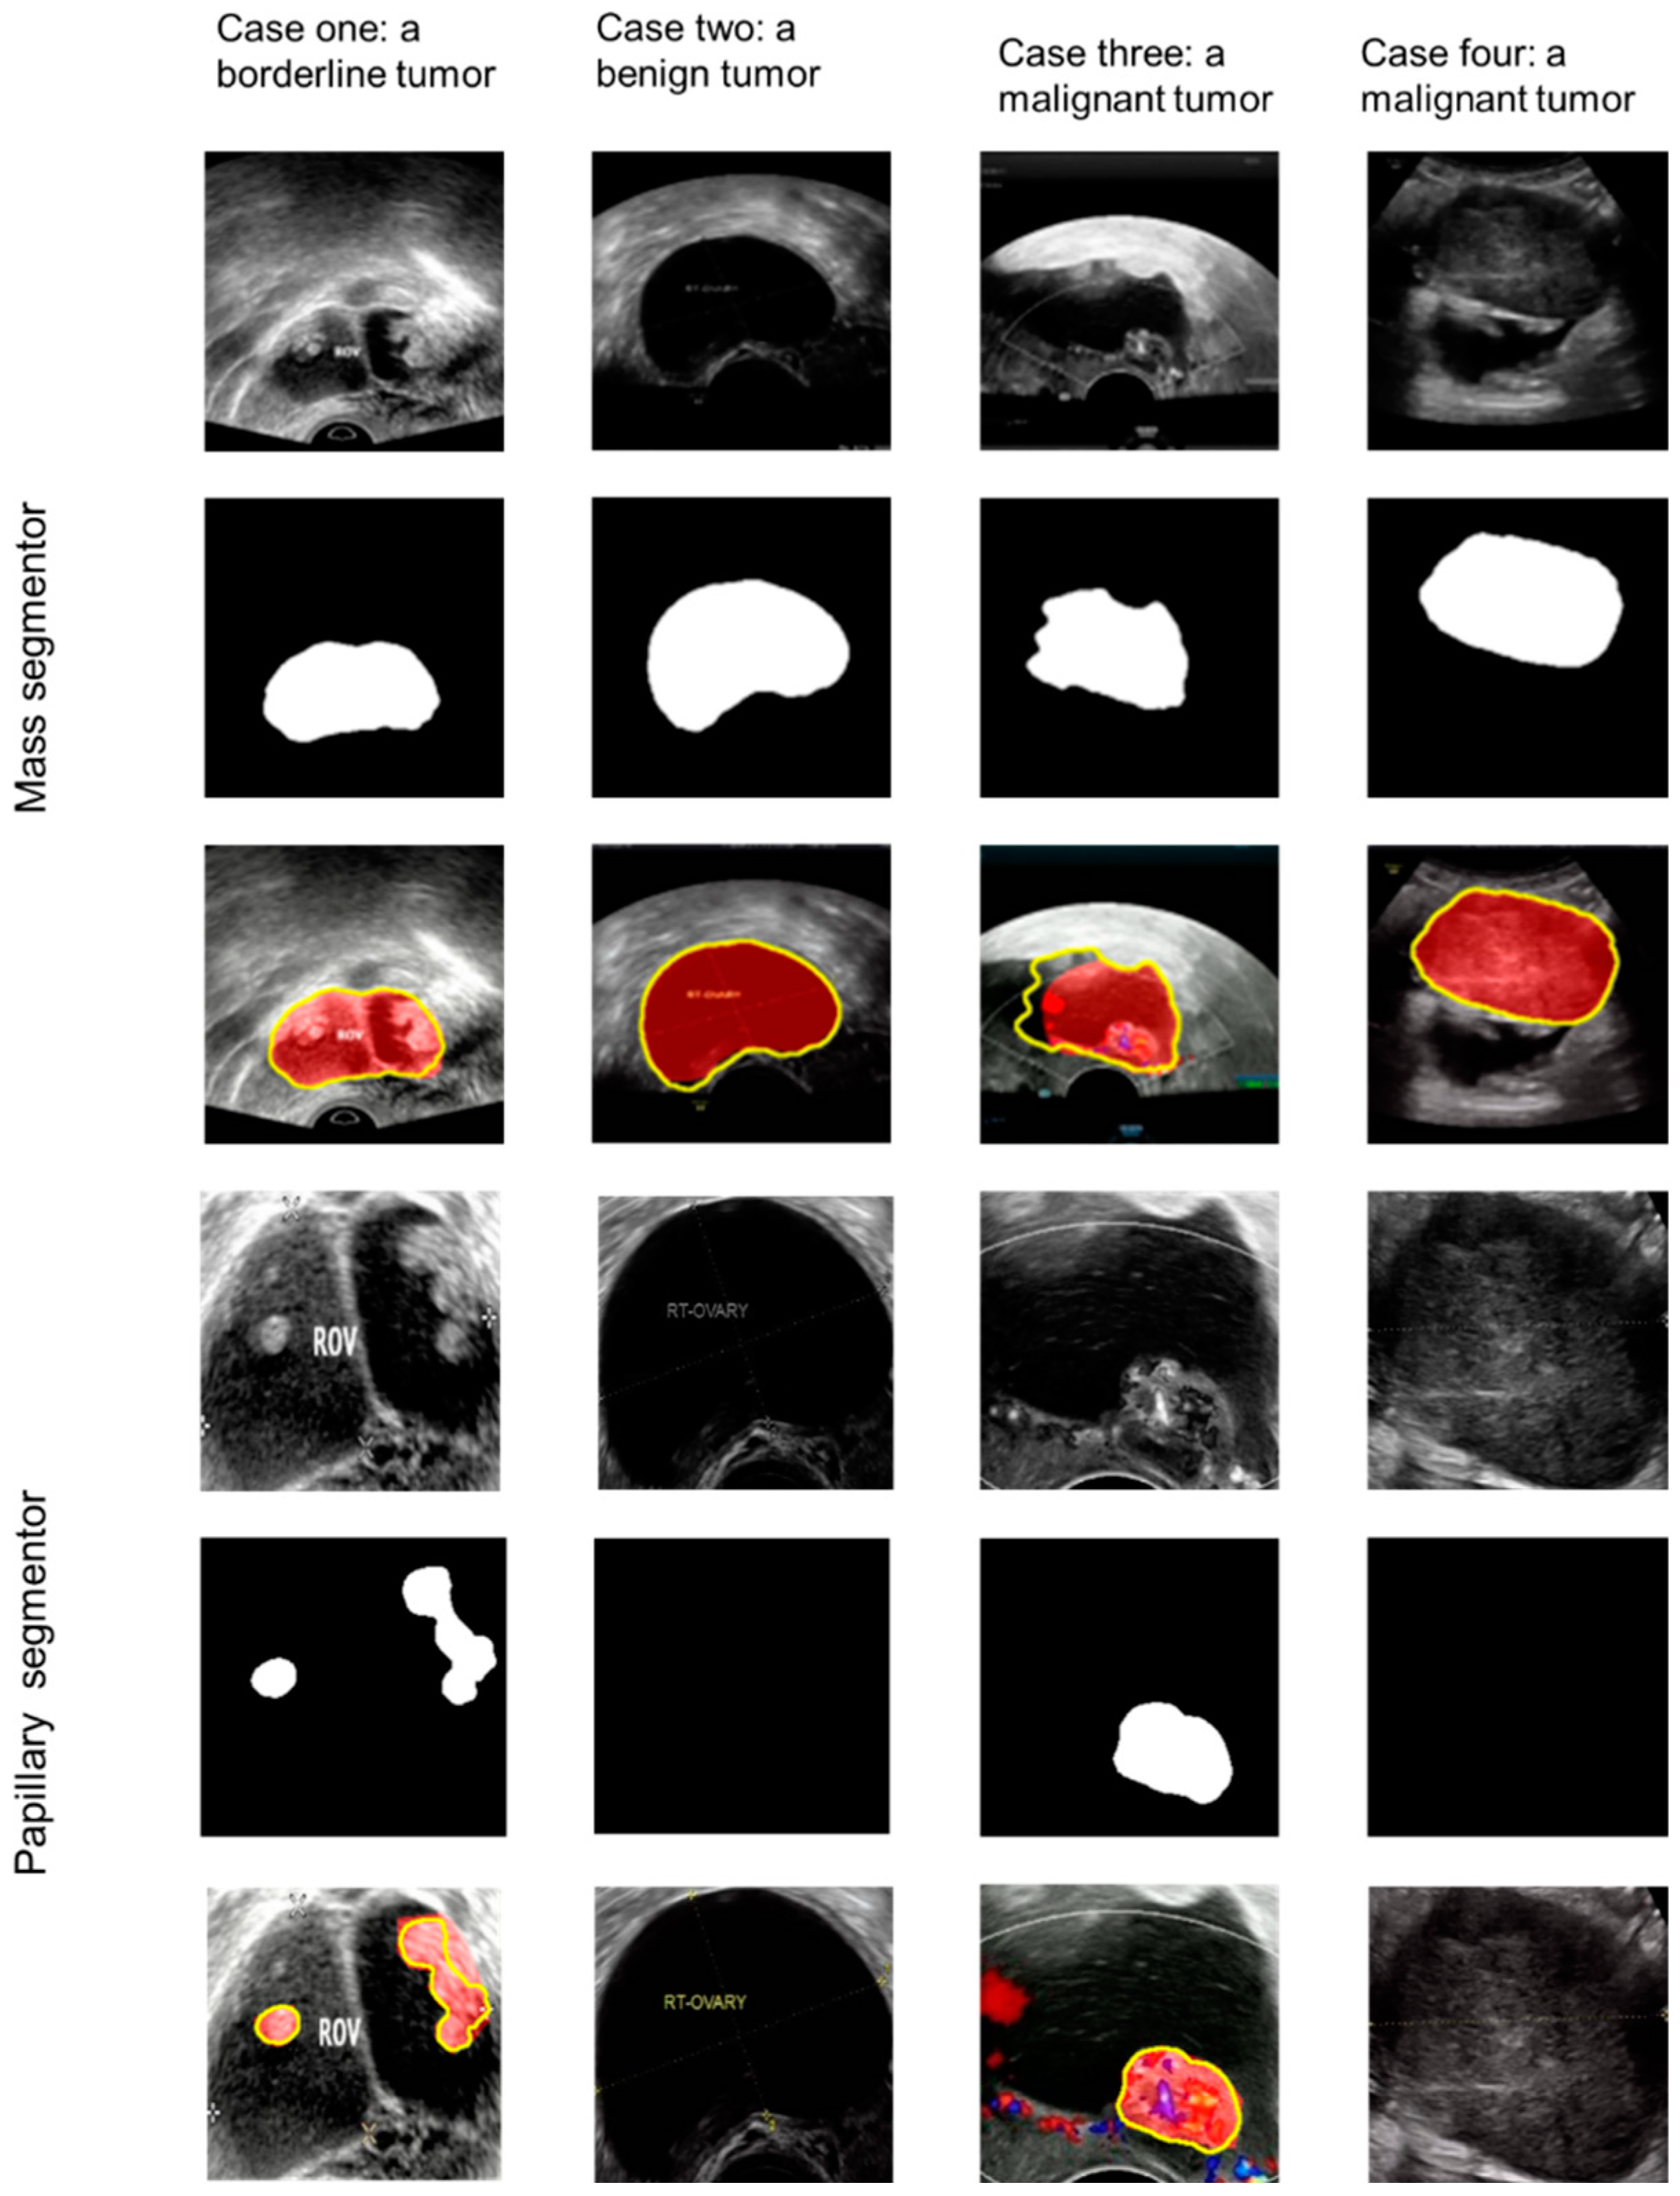

The papillary projection segmentor located the projections accurately. The dice score was 0.864 for the internal validation dataset, 0.852 for external test dataset 1, and 0.855 for external test dataset 2. Figure 3 shows the results of four cases of the mass segmentor and the papillary segmentor.

Figure 3.

Case one shows a borderline tumor with papillary projections; case two shows a benign tumor without papillary projections; case three shows a malignant tumor with a papillary projection; case four shows a malignant tumor without papillary projections. The top three rows show the process of the mass segmentor; the three rows below show the process of the papillary segmentor. Yellow line: the result of the mass segmentor or the papillary segmentor; red area: ground truth.